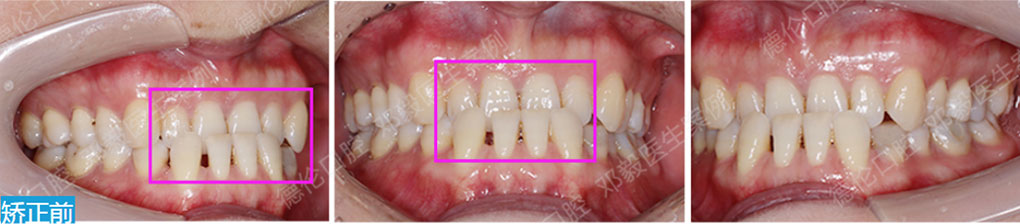

- 【診斷】

先天缺少下切牙2顆

上前牙錯(cuò)位于下前牙后側(cè),前牙無(wú)咬合功能,上牙槽及上唇后縮

打造醫(yī)生:德倫口腔正畸中心鄧毅醫(yī)生

- 【治療方案】

調(diào)整弓形及配合Ⅲ類牽引,實(shí)現(xiàn)頜跳躍

矯治前后對(duì)比

牙列整平排齊,前牙內(nèi)收;覆蓋、覆合正常;尖牙和磨牙達(dá)到中性關(guān)系;上下中線對(duì)齊;下頜后縮改善